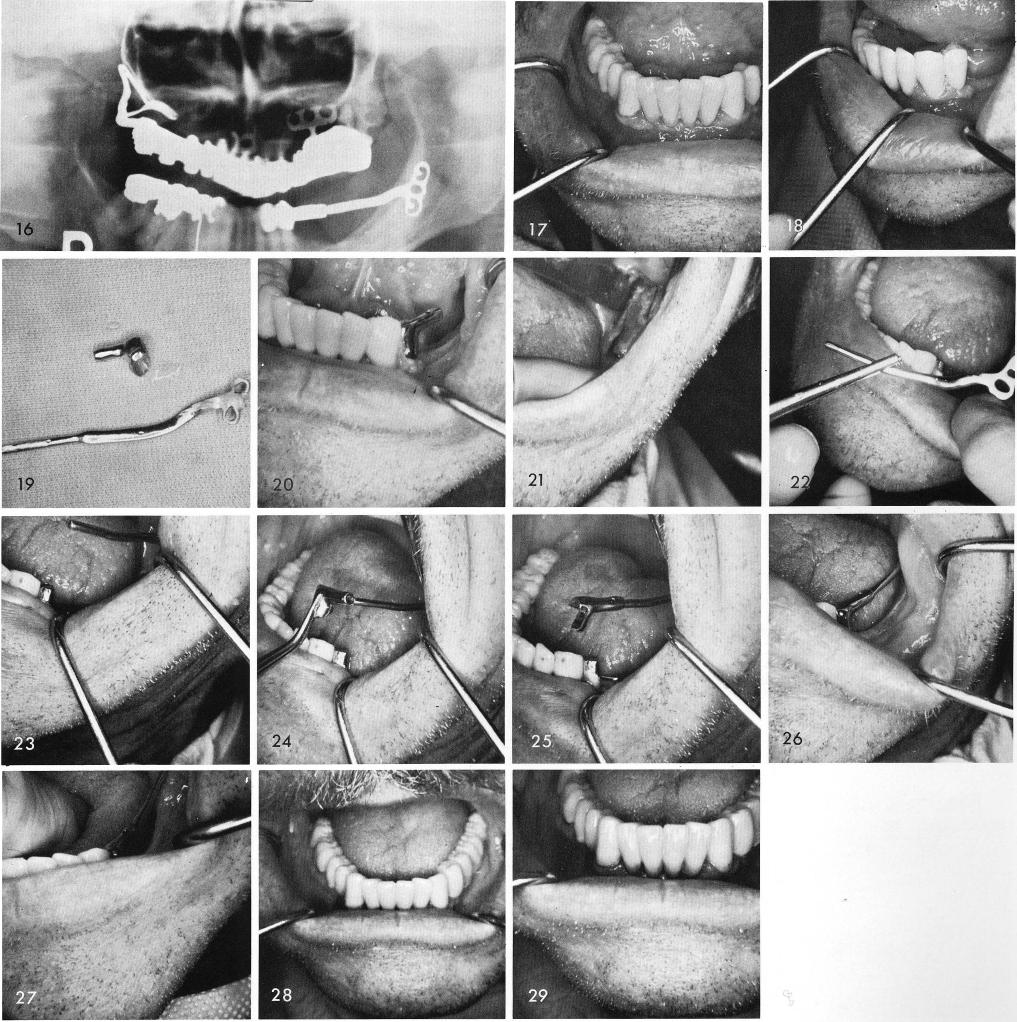

This case shows an existing fixed prosthesis with a cantilevered left bicuspid that was purposely left when the posterior teeth underneath the left side of the bridge had to be removed, fig. 17. The bicuspid pontic is then prepared for a telescopic coping with a distally extended hollow tube to engage the anterior portion of the ramus cable, figs. 18, 19, 20. The groove is made on the buccal side of the ramus, fig. 21, and the ramus blade is tapped into proper "upward" alignment, figs. 22, 23. The hollow tube is fitted over the cable, figs. 24, 25, and the coping is tapped downward to engage the prepared cantilevered pontic, fig. 26. One week later the tissue

1 Mandibular fixed prosthesis with a cantilevered bicuspid